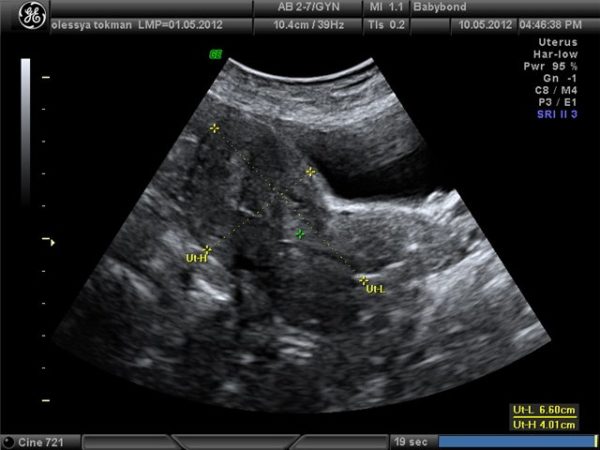

- Ультразвуковое исследование малого таза даст возможность определить величину матки, толщину стенок (при эндометрите они увеличиваются), также даст возможность установить другие сопутствующие патологии;

Одним из самых эффективных методов диагностики эндометрита является УЗИ-диагностика. Она не только позволяет выявить заболевание и провезти дифференциальную диагностику, но и является безболезненной для пациента. Ультразвуковое исследование обладает высокой точностью и применяется как скрининговое обследование женского населения. Его преимуществами являются точность, неинвазивность, дешевизна, безопасность для пациента.

Эхопризнаки недуга

Диагностировать эндометрит при помощи УЗИ можно только на второй стадии развития заболевания.

Исследование нужно проводить за несколько ней до начала менструации, это связано с тем, что патологические процессы в этот период времени наиболее выражены, и обнаружить патологию становится значительно легче.

При помощи УЗИ можно выявить следующие эхографические признаки эндометрита:

- Утолщение слизистого слоя матки в результате гиперплазии эндометрия;

- Утолщение миометрия при вовлечении мышечного слоя матки в патологический процесс.

- Изменение формы матки и анатомического положения, благодаря образованию спаек в полости матки;

- Изменение размеров матки, из-за скопления в ней экссудата;

- При длительно течении заболевания, можно обнаружить спаечный процесс, он выявляется как множественные очаги с повышенной эхоплотностью.

УЗИ метод является ориентировочной диагностикой эндометрита, позволяет его дифференцировать от другого рода патологий.

Для более точно установления диагноза применяется микробиологический метод, который проводится после взятия мазков.

Заподозрить острый эндометрит при ультразвуковом исследовании достаточно сложно, так как при УЗИ выявляется не столько признаки эндометрита, сколько признаки спаечного процесса и структурных изменений строения матки.

Поэтому при помощи эхо-диагностики обычно диагностируется хронический эндометрит.

Признаками хронического эндометрита являются:

- Уменьшение толщины эндометрия (видно на фото);

- Изменение строения слизистой оболочки матки;

- Расширение полости матки, благодаря скоплению экссудата;

- Наличие кист и газовых пузырьков;

- Распространенные диффузные патологические изменения в миометрии, слоя, находящегося вблизи эндометрия.

Признаками острого эндометрита являются:

- Утолщение внутреннего слоя матки (воспаление);

- Изменение в строении слизистого слоя матки;

- Увеличение матки.